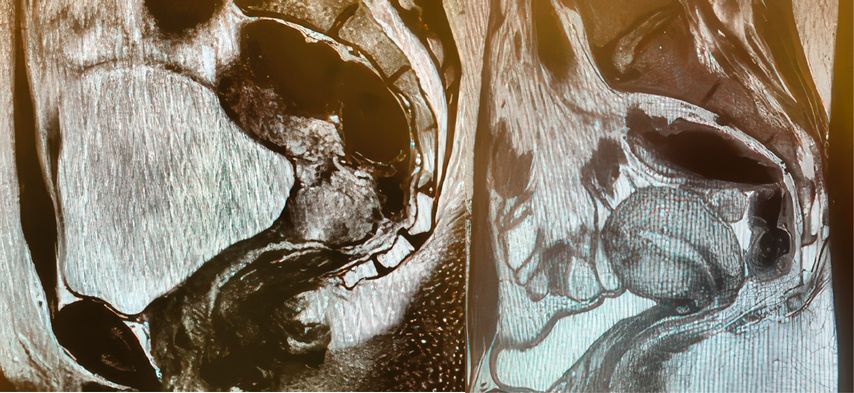

Bei nodal-negativen Tumoren mit einem Durchmesser zwischen 2 und 4cm können bei entsprechend motivierten Patientinnen ausserhalb der Leitlinien individuelle Therapieoptionen diskutiert werden, wie beispielsweise eine abdominale radikale Trachelektomie oder eine neoadjuvante Chemotherapie mit anschliessender Konisation (Abb. 1a und b).

Abb. 1: Präoperatives (a) und postoperatives (b) MRI des Beckens einer jungen nulligraviden Patientin im FIGO-Stadium IB2 mit einem Plattenepithelkarzinom der Zervix, die mit einer radikalen abdominalen Trachelektomie behandelt worden ist. Die Patientin ist drei Jahre nach der Behandlung tumorfrei